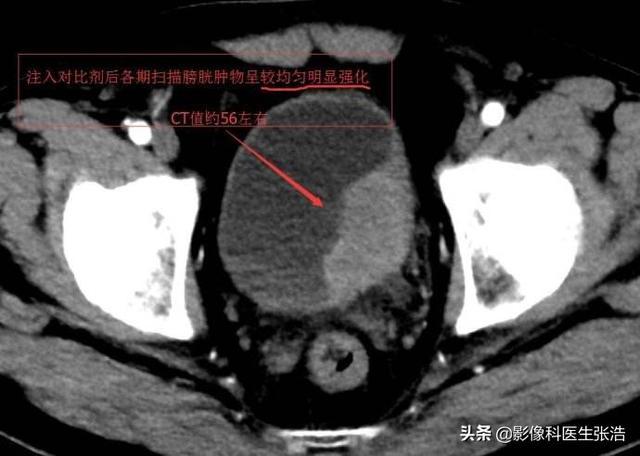

患者ct结果—箭头处为膀胱肿瘤

经过增强泌尿系ct,膀胱镜(活检)等检查,确诊为高级别尿路上皮癌,且